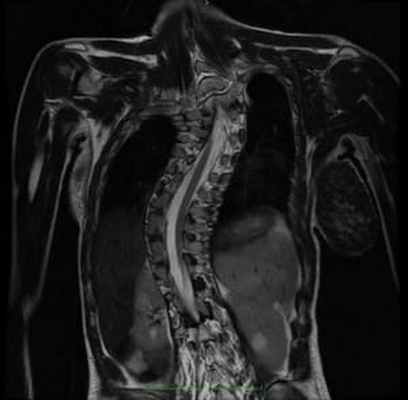

Рисунок 5.- МРТ позвоночника с вертикальным разрезом: виден сколиоз, внутри позвоночного канала спинной мозг не следует изгибам позвоночника, что указывает на наличие значительного натяжения спинного мозга.